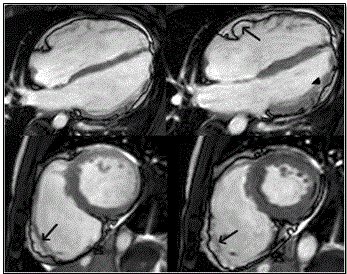

The main challenge of cardiac MRI in imaging ARVD patients is the lack of well-defined sensitivity and specificity such that the quality of images is operator dependent and findings subject to individual interpretation (inter-observer variability) [20,79]. Marcus et al. [68] analyzed findings of American Multidisciplinary study on clinical presentation and diagnosis of ARVD and reports variation between MRI diagnosis of referral center and core laboratory. Core laboratory did not confirm 29% of diagnosis confirmed by the referral center [68]. Cine-MRI promises better detection by the ability to estimate RV volume and wall motion abnormalities due to akinesia, dyskinesia and aneurysms [1]. Figure 7 shows cardiac MRI four-chamber and short-axis imaging planes of ARVD patient with predominant RV abnormalities. The left panels show end-diastolic and right panel end-systolic. The arrow in the 4-chamber end-diastolic image shows subtricuspid dyskinesia while arrows in the short axis images show RV free wall aneurysm – systolic and diastolic bulging.

Figure 7: MRI - 4 Chamber (Top Panels) and Short Axis (Bottom Panels) or ARVD Heart

Top panel shows 4-chamberand bottom panels short-axis view of bright blood images in ARVD patient with predominant RV abnormalities. Left panels end-diastolic images and right panel end-systolic images. Sub-tricuspid dyskinesia in the end-systolic 4-chamber (arrow) and RV free wall aneurysms in both short axis images (arrows). Source: Te Riele et al. 2014, p.5 [79]

Further, Figure 8 shows MRI images of ARVD patient with predominant LV abnormalities. Bright blood images/LGE MRI (bottom panels) show dilated LV and mid-myocardial pattern in basal septum and basal lateral walls (arrows)

Figure 8: Top Panels – Horizontal Long Axis; Bottom Panels Bright Blood/LGE

Top panels show horizontal long axis bright blood and bottom panels show LGE images of ARVD patient having predominant LV abnormalities. There is dilated LV in the bright blood images. LGE is shown in a mid-myocardial pattern in basal septum and basal lateral walls (bottom panels arrows). Source: Te Riele et al. 2014, p.6 [79]